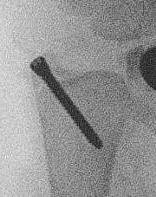

Xray

DRUJ disruption

- widened space between radius and ulna on AP

- dorsal subluxation / dislocation of ulna on lateral

- radial shortening > 5 mm

- ulna styloid fracture

Shortening of radius with disruption of DRUJ on lateral

Widening of interval between radius and ulna / clear disruption of DRUJ

Concern for disruption of DRUJ on lateral